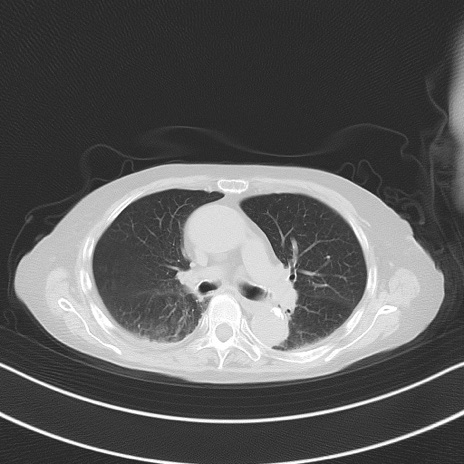

横断像